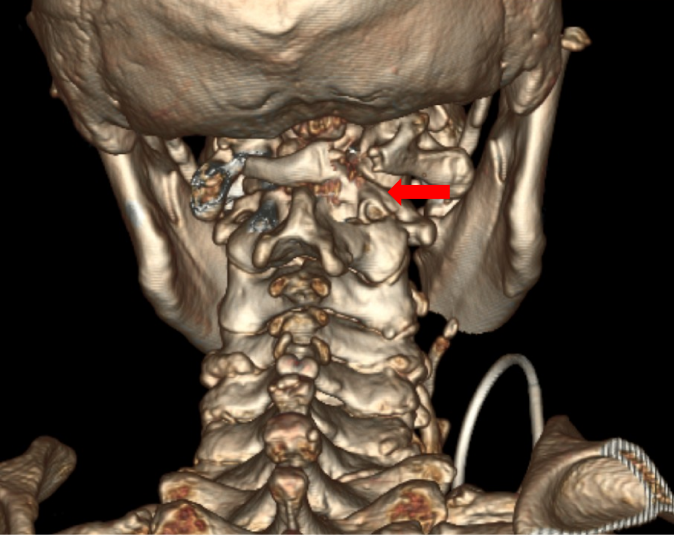

患者王先生已72岁,四肢乏力进行性加重10年,伴左下肢跛行4年,因担心需要手术治疗而没有正规就医。近期已无法独立行走,经推荐来到苏大附四院姜为民主任门诊就医。王先生的查体结果表现出明显的高位脊髓损伤症状:左上肢肌力下降至4级,左侧霍夫曼征、踝阵挛及巴彬斯基征均为阳性,左足下垂;右侧病情稍轻。影像学检查显示“游离齿状突畸形”——即第二颈椎(C2)齿状突发育异常并游离,后缘异常增生导致上段颈髓严重受压,脊髓功能受损使得患者近年来行走能力不断下降,并因此频繁跌倒,这对患者的生命安全构成了极大威胁。

颈椎手术尤其是上颈椎手术的难度与风险很高,常被誉为刀尖上的舞蹈。术前的全面检查显示,该例患者与常见的上颈椎游离齿突畸形不同——引起颈髓损伤的主要原因不是寰枢椎不稳,而是齿突后方的异常骨性增生严重压迫脊髓所致。目前常用的手术解除脊髓压迫方法是经口咽途径直接切除游离的齿突及增生的骨性结构,再从后方行枕颈固定融合。但是这种手术不仅难度高而且有大量并发症风险,更是会令患者失去头部旋转功能的风险。最初姜主任团队一度考虑采用该常规手术方案,但对于这位72岁的高龄患者而言,创伤与风险是巨大的。